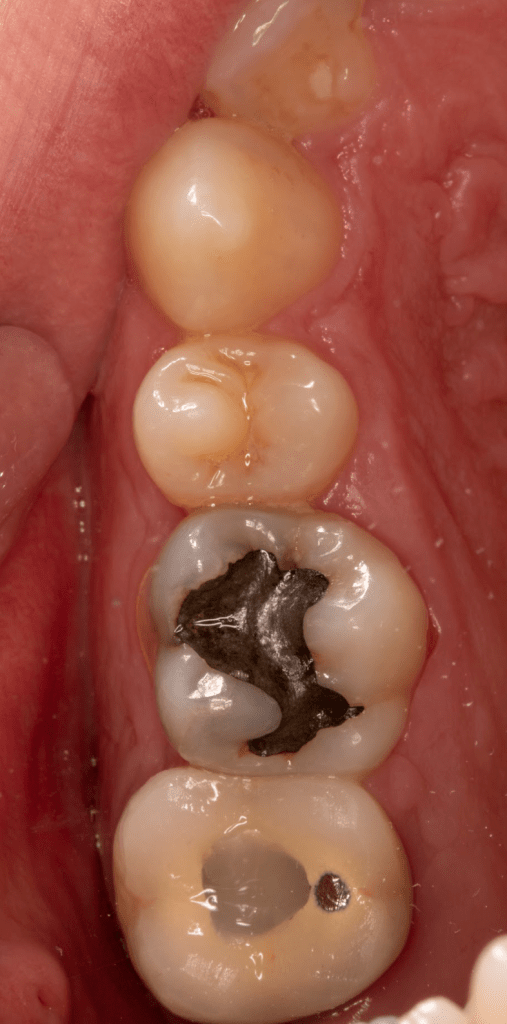

Fisura, remoción amalgama para explorar

Reco preendo + 4 conductos molar superior